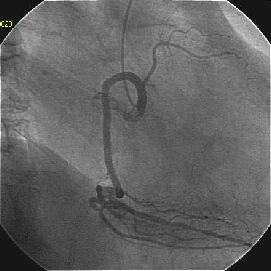

�܂�pre CAG.

Crush�̎�Z�B

Crush���KBT.

�ŏI�o���オ���IVUS�BIVUS��170507��septal���}����170509������2mm��O��